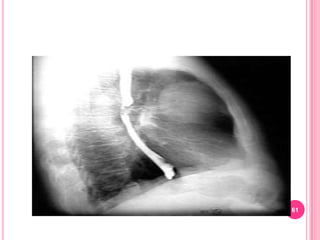

If barium studies are to be performed, nurse should make sure they are scheduled after this test…..why?5. DNA Testing – Pre clinical diagnosis to identify persons who are at risk for certain GI disorders  (gastric cancer, lactose deficiency, inflammatory bowel disease, colon cancer).6.  Imaging StudiesX-ray and contrast studies 	 Upper GI series or barium swallow>  Double contrast studies – administration of thick barium suspension followed by tablets that release carbon dioxide in the presence of water. (Early superficial neoplasms are identified)> Enteroclysis – a double contrast study of the entire small intestine by infusing continuously of 500-1000ml of thin barium sulfate suspension followed by methylcellulose and observed through fluoroscopy.  Up to 6 hours. For diagnosis of Partial small-bowel obstructions or diverticula.

7.  Upper GI series or Barium SwallowNursing InterventionsPatient need to maintain low-residue diet for several days before the test.

NPO after midnight before the test.

Physician may prescribe laxative

Discourage smoking on the morning before the examination

Withholds all medications

Follow up care after the procedure, fluids must be increased, monitor patient’s stool color, laxative or enema may be needed.8.  Lower Gastrointestinal Tract StudyBarium Enema